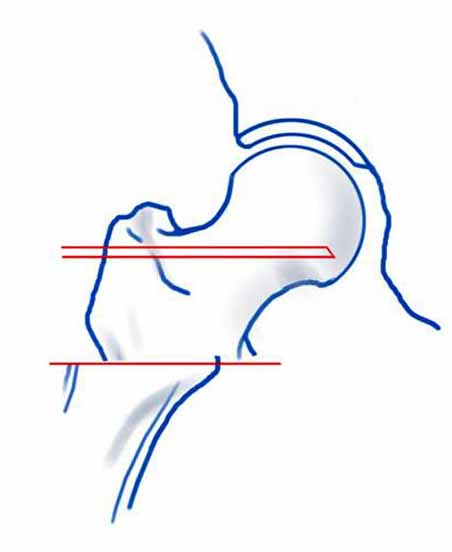

На снимке положение клинка идеальное, но шейка в ротации. Из-за неправильного расчета остеотомии не удалось латерализовать диафиз, и конечность находится в чрезмерном вальгусе. При укорочении с вальгусом увеличивает стресс в зоне между пластинами, и конструкция не выдерживает, и при малой травме может осложниться стрессовым переломом.

Для предупреждения чрезмерного вальгуса во время операции сразу ниже клинка снаружи выше линии остеотомии укладывается костный фрагмент, взятый из остеотомии, который переводит диафиз из медиального положения латерально.

В 120 градусной или в любой реконструкционной клинковой пластине главным является проксимальный, т.е. ближайший к остеотомии винт. Чем ниже остеотомии находится винт, тем больше увеличивается момент рычага, что может привести к несостоятельности (поломке) конструкции. Для вальгусной остеотомии достаточной бывает пластина с двумя отверстиями, но при этом варианте, возможно, длинная пластина пригодится?

Расположение клинка и степень сращения в зоне остеотомии трудно увидеть по одной проекции, и поэтому желательно дополнить исследования КТ и боковыми рентген снимками.